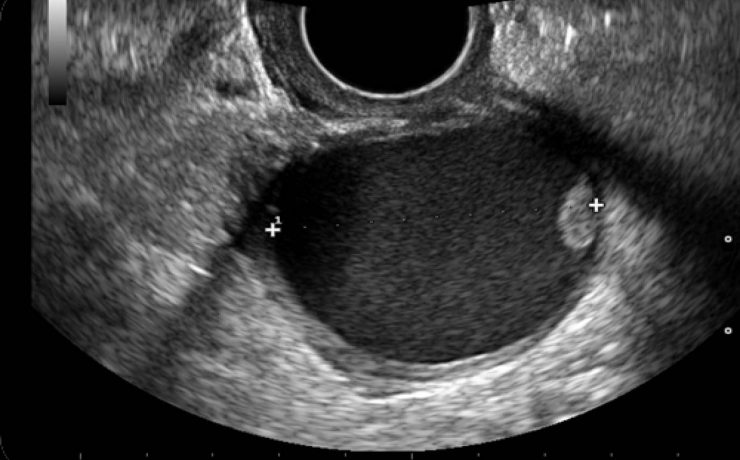

La muerte u óbito fetal se define como la ausencia de latido cardíaco, pulsación de cordón, respiración espontánea y movimientos del feto, antes de la separación completa del cuerpo de la madre. Aunque en algunos países se considera desde que el feto pesa 350 g y en otros se utiliza